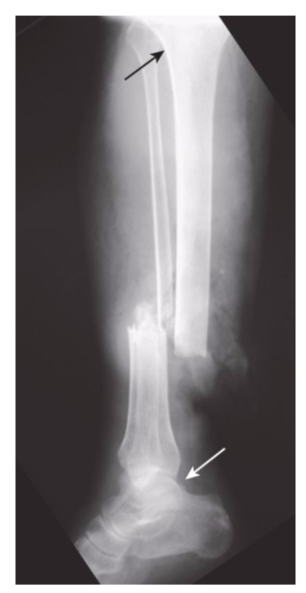

Rotation.

An unusual abnormality in fracture positioning, almost always involving the long bones, which describes the orientation of the joint at one end of the fractured bone relative to the orientation of the joint at the other end of the fractured bone. To appreciate rotation, both the joint above and the joint below a fracture must be visualized, preferably on the same radiograph. In this patient, the proximal tibia (black arrow)is oriented in the frontal plane, and the distal tibia and ankle (white arrow)are rotated and oriented laterally.